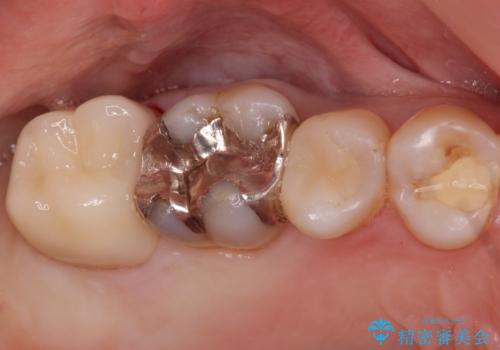

奥歯がしみて痛い

- 冷たいものがしみて飲み物が飲めないとの事で来院。

歯肉が退縮していたので歯周外科手術(歯茎の移植手術)か被せ物で覆う(歯肉退縮しているところまで覆う)の提案をしたところ被せ物がいいとのことでしたので

被せ物の治療のご案内になりました。

適合の良い被せ物が入りました。

冷たいものがしみなくなり大変満足してもらいました。

一つ前の歯も後に染みてくる可能性があるとの事で被せ物をするか検討中です。